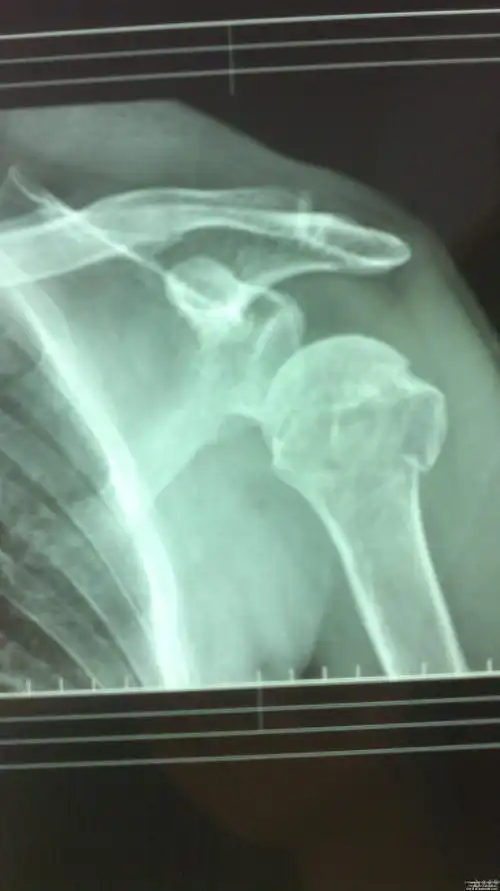

肩关节损伤

肩盂骨折

肩关节半脱位原因

肩部骨折会有局限性疼痛,可导致肢体功能完全丧失,并发症有休克

当摔倒时手外展着接触地面或手持重物,肩关节突然外展上举或扭伤而